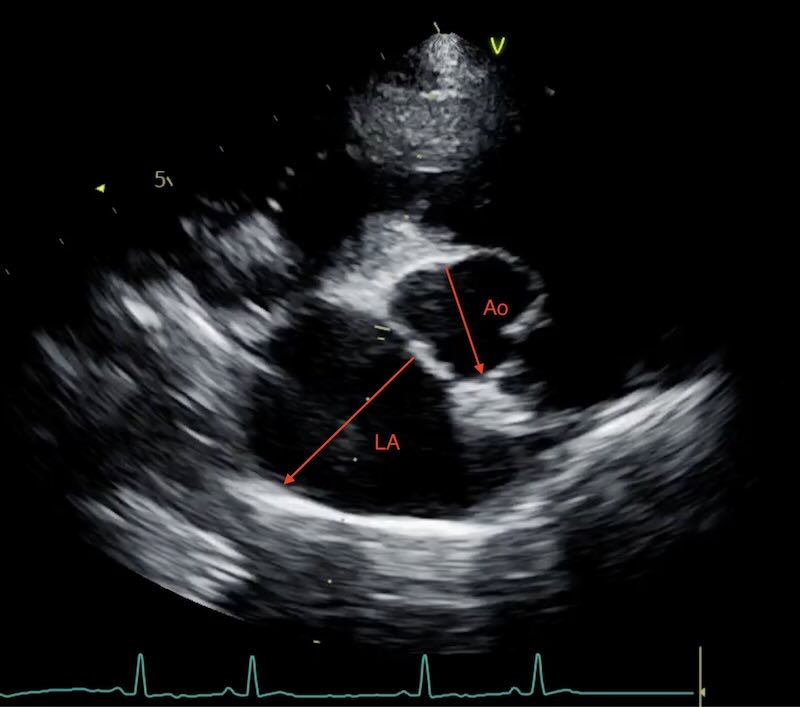

Cats can have their heart ‘tipped’ a long way forwards, creating a lot of variation in the position of the ‘long axis’ and ‘short axis’. This is especially pronounced in older cats. In addition a rotation effect often means the LA:Ao measurement ends up being quite a vertical one:

Also cats sometimes enlarge their atrium in length rather than width. In cats, we use the “Rule of Thirds” for a quick subjective check: on a long-axis view, the left atrium should occupy roughly one-third of the total length of the heart silhouette. If the atrium looks like it is dominating the image, or if it has lost its “square” shape and become globular, the cat is at high risk for blood stasis and ATE.